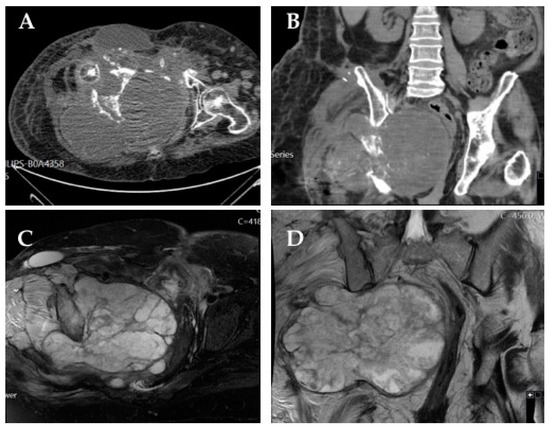

- Bloem, J.L.; Reidsma, I.I. Bone and soft tissue tumors of hip and pelvis. Eur. J. Radiol. 2012, 81, 3793–3801. [Google Scholar] [CrossRef]

- Rajiah, P.; Ilaslan, H.; Sundaram, M. Imaging of sarcomas of pelvic bones. Semin. Ultrasound CT MR 2011, 32, 433–441. [Google Scholar] [CrossRef]

- Park, S.K.; Lee, I.S.; Cho, K.H.; Lee, Y.H.; Yi, J.H.; Choi, K.U. Osteosarcoma of pelvic bones: Imaging features. Clin. Imaging 2017, 41, 59–64. [Google Scholar] [CrossRef]